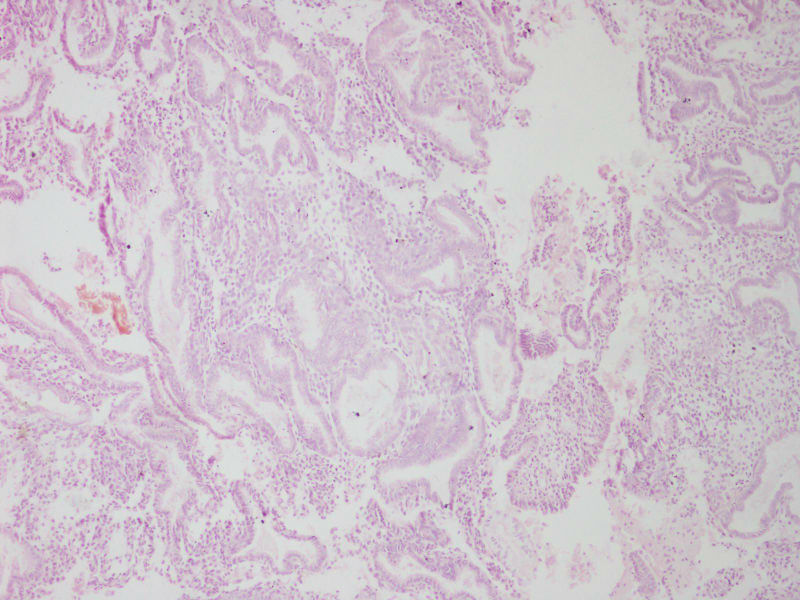

35反复腰腹胀痛伴白带异常1年加重3LMP109,送检日期1021

• 宫内膜图1

图1

子宫内膜不规则增生

分泌期宫内膜

分泌期改变子宫内膜

片子做得太差了,和我们科有一拼了。感觉宫内膜呈分泌期改变

分泌期子宫内膜

分泌期宫内膜,间质有慢性炎细胞浸润

分泌期子宫内膜像。